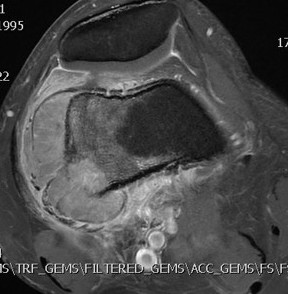

MRI

Low signal intensity of T1 / high signal intensity on T2

- intramedullary extent

- skip lesions

Significant soft tissue mass with significant edema

Ewing's femoral diaphysis, subtle on xray with large soft tissue component

Ewing's distal femur